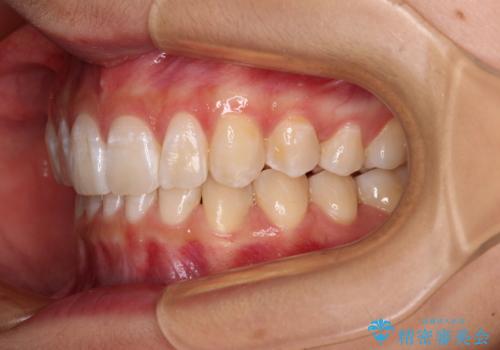

深い咬み合わせで前方に煽られた前歯 高校生のインビザライン矯正治療

- 前歯の隙間と前方に飛び出していることを気にして来院された患者様です。

奥歯の咬み合わせを見ると、上顎が下顎に対して相対的に前方にありました。

咬み合わせも深くなっていたため、上顎臼歯を後方に移動させつつ、下顎の小臼歯を直立させ、奥歯の咬み合わせを改善する必要があります。